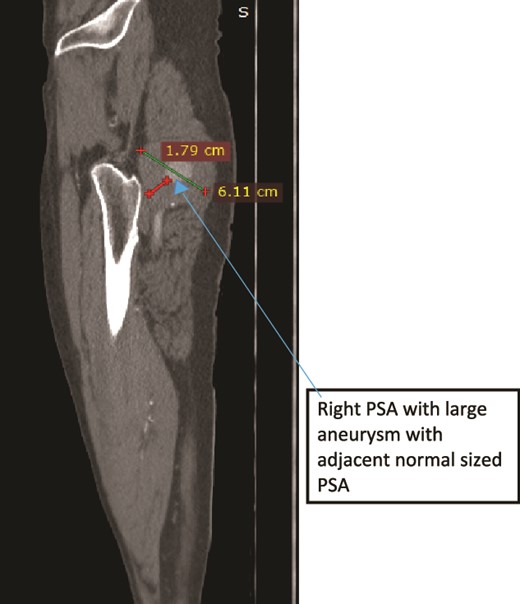

A 47-year old male patient presented with right thigh and leg pain of 1 year with associated decreased muscle mass and right gluteal area swelling with pain which radiated to his posterior thigh for 6 months. Pain was exacerbated by lying or sitting. He was a smoker for the past 15 years but discontinued 2 months prior. On examination, the right LL muscles were atrophic with gross discrepancy in muscle mass. He had a 4 × 3 cm2 pulsatile palpable, slightly tender mass over the outer upper quadrant of the right gluteal region. He had non-palpable pulses in the right PA, DPA, or PTA. Power was 4/5 in the right LL with intact sensory function. Preoperative ABI was not recordable. CTA showed bilateral PSA with right gluteal sciatic artery thrombosed aneurysm and distal occlusion (Figs 4–6) After delay due to patient acquiring COVID, he was subsequently operated and underwent right PSA ligation and aneurysm hematoma evacuation in prone position through posterolateral buttock curvilinear incision approach without aneurysm wall excision. The patient then underwent CFA- to PTA-reversed GSV bypass after repositioning. Postoperatively ABI on the first post op day was 0.8. The patient was unable to afford PO anticoagulant and was discharged with antiplatelet (low-dose aspirin), which the patient discontinued after 1 month. On the 2-month postoperative follow-up, the patient had recurrence of burning sensation over the right leg with absent distal pulses but disappeared from follow-up thereafter.

Case 2—sagittal images of LL CTA of the right LL arteries showing large aneurysm with surrounding thrombus with adjacent normal-sized PSA.